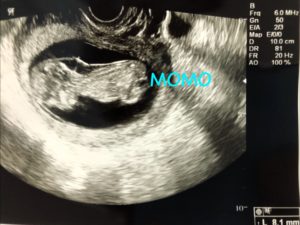

妊娠12週。助成の紙を使っての初めての妊婦健診の日。

今日もエコーで心拍確認出来て安心した。

すると、いつもすぐに終わるエコーがちょっと長い。

「これがさっきから気になる」

そう言われてエコーを見ると…なんだか首の後ろが厚くなっている。

そう言ってエコーの写真をくれた。

すぐにネットで調べてみると胎児の首の後ろに出来る浮腫をNTと言うらしかった。

正常でも浮腫んでしまう子も稀にいるらしいが、ダウン症や心臓の先天性奇形などの影響でよく見られる特徴との事。

NTが厚いほど、深刻な状態の事が多いようだ。

NTをきちんと測るには11週〜13週の間に資格を持った医師が普段のエコーよりも精密な機械を用いて測らないといけないらしかった。